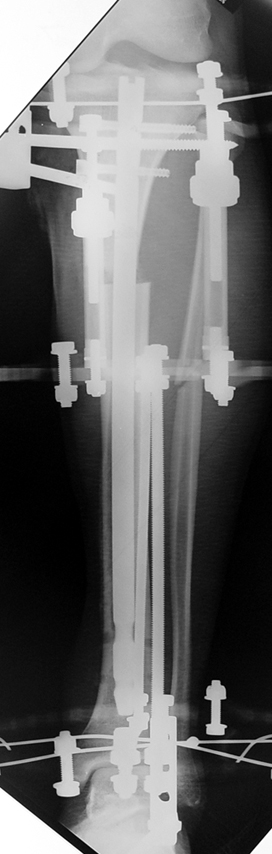

The patient lies is supine position at a traction table and legs are crossed with the uninvolved leg at the bottom. The medullary cavity is penetrated through piriform fossa using the standard method, and medulla is reamed 1.5 mm thicker than the nail to be used, over a guidewire. Proximal femur is reamed more, because the intramedullary nail is thicker proximally. The osteotomy site is planned at the X-Rays. It is important that at least 8 cm. of nail remains distal to the osteotomy site after the completion of the lengthening procedure. Percutaneous corticotomy is performed. The guide wire is advanced distally in order to measure the length of the nail. An intramedullary nail of apropriate length is placed. In the end, the nail is interlocked proximally, a suction drain is placed and the fist step of the operation is completed.

The application of the external fixator: Three Schanz screws are placed distally and three screws are placed proximally. At least 1 mm of distance shall remain between the screws and the nail.

In selected cases, we prefer to use a combination of a unilateral dynamic axial fixator and an interlocked intramedullary nail, in order to protect the length and alignment after the completion of the lengthening procedure. As a prerequisite for this technique, the narowest diameter of the medullary cavity shall be wider than 7 mm and the length of the nail segment distal to the osteotomy site shall be at least 8 cm. after the completion of the lengthening procedure.The intramedullary nail neutralizes shear and bending forces on femur during lengthening, shortens external fixation time, and protects newly formed bone against fractures. In our series, subtrochanteric osteotomy was performed in one case. No varus angulation occured despite the intramedullary nail.

Ilizarov stressed the significance of endosteal blood circulation for distraction osteogenesis. Although we placed the intramedullary nail after reaming the femur in all cases, the time for callus formation was not longer than expected. Thus we found that there is no slowing in the rate of new bone formation due to disruption of medullary blood flow. The rationale of this finding is revascularization that occurs following reaming of the medullary cavity, the fixation stability with the intramedullary nail and early functional weight bearing. The potential disadvantages of a combined use of external and internal fixation metods are increased blood loss, intramedullary infection, risk of fat embolism and excessive metal load.The most fearsome complication is a deep intramedullary infection (panosteomyelitis) triggered by pin tract infection.No such complication was encountered in our series. In order to avoid this complication, after the completion of lengthening the nail shaill be interlocked from the medial side, and contact of internal and external fixator pins shall be avoided.